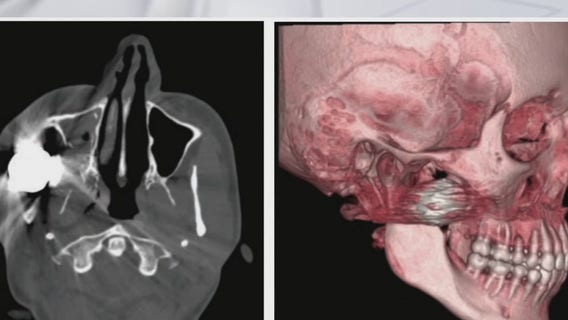

Austin surgeons shocked by injuries protesters sustained by bean bag rounds